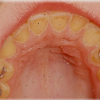

Diasteem

Diasteem – vahe esimeste hammaste vahel. Esineb 50%-l 6-8 aastastel lastel. Kuni 2 mm diasteemi puhul on, peale lateraalse intsisiivi ja silmahamba lõikumist, võimalik diasteemi iseeneslik sulgumine. Diasteem, mille suurus...